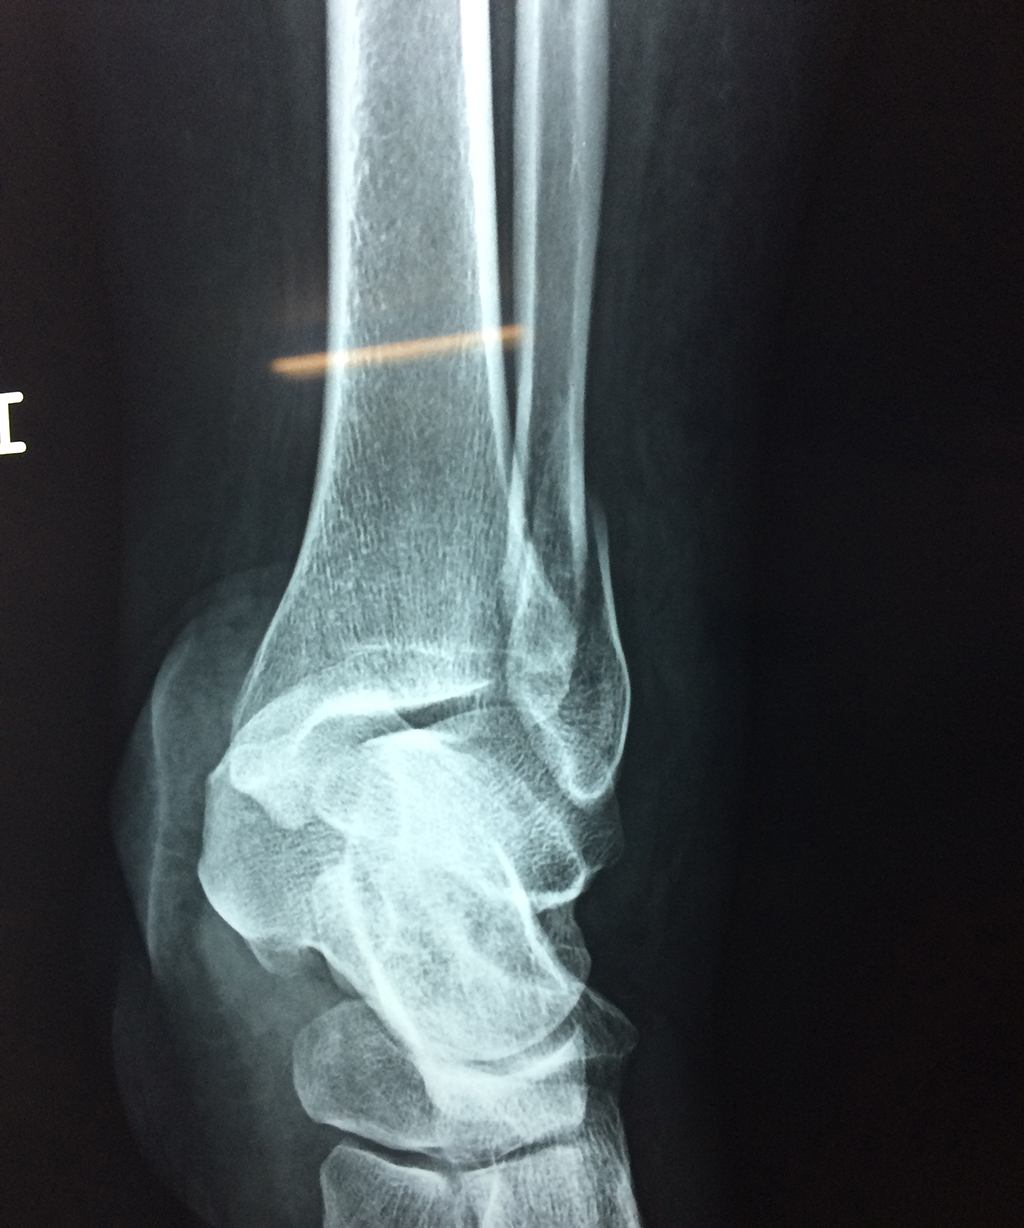

Una fractura de tobillo es la rotura de uno o más de los huesos del tobillo. Estas fracturas pueden ser:

Algunas fracturas de tobillo pueden requerir cirugía si:

- Los extremos de los huesos están desalineados entre sí (desplazados).

- La fractura se extiende hasta la articulación del tobillo (fractura intra-articular).

Cuando se necesita cirugía, es probable que esta implique el uso de clavijas de metal, tornillos o placas para sostener los huesos en su lugar mientras la fractura se consolida. Los elementos de soporte pueden ser temporales o permanentes.